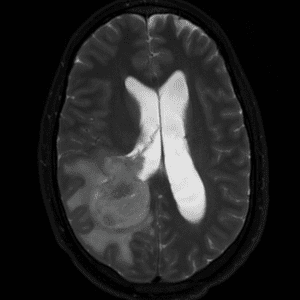

Case #26

Intraventricular glioblastoma